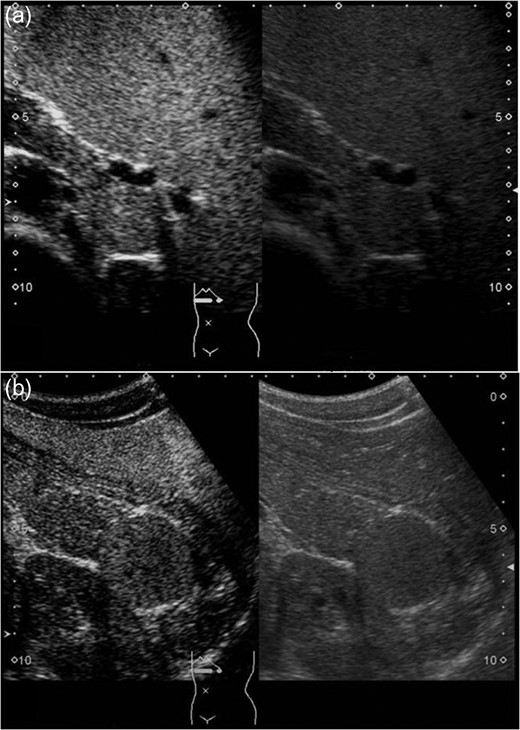

Sonazoid-enhanced ultrasonography Presplenectomy enhanced ultrasonography shows hypervascularity in the mass, located near the pancreatic tail and suspicious for an accessory spleen. The mass grows rapidly to 4 cm by 1 year after splenectomy (a: before splenectomy, b: after splenectomy).

A 16-year-old boy was admitted with a rapidly growing pancreatic mass. He had received a diagnosis of HS based on the following: the need for a blood transfusion to treat anemia after birth, a history of hemolytic anemia, and a family history of HS. He had often undergone medical examinations for anemia and jaundice in junior and senior high school. When he was 15 years old, he visited our hospital because of the rapid onset of jaundice. Radiological examinations, such as computed tomography (CT) (Fig. 1a–c) and magnetic resonance imaging (MRI) (Fig. 2a–c), showed a huge spleen and a 2-cm mass near or in the pancreatic tail. Sonazoid-enhanced ultrasonography showed hypervascularity in the mass, which appeared to be located near the pancreatic tail and raised suspicions about an accessory spleen (Fig. 3a). The patient underwent a successful splenectomy by laparotomy, but the mass found on the preoperative examination could not be found by inspection and intraoperative ultrasonography (Fig. 4a and b). The mass grew rapidly to 4 cm one year after splenectomy, as shown on the radiological examinations (Figs 1d–f, 2d–f and 3b), but a recurrence of HS with anemia or jaundice did not develop. However, he underwent successful laparoscopic surgery to aid in the differential diagnosis. After the adhesions of the omentum to the abdominal wall were detached, the laparoscopic ultrasonogram revealed the mass in the pancreatic tail. He underwent laparoscopic distal pancreatectomy (Fig. 4c and d), and he had no clinical symptoms or signs of local infection or sepsis. A CT on the ninth postoperative day showed a small peripancreatic collection (Grade B: the clinical grading of postoperative pancreatic fistula). He was discharged on the 11th postoperative day. The resected specimen revealed the intrapancreatic mass that was covered with pancreatic tissues, and the intrapancreatic mass was an accessory spleen (Fig. 4e).